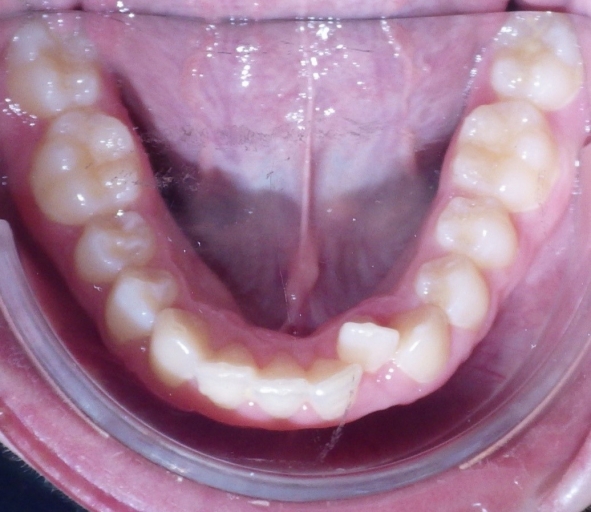

The arch form is also an important factor to evaluate in a Class II pattern. If the upper arch form is narrow, the upper incisors are more protrusive with an increased overjet. (Fig. 5 and 6) The maxilla appears “V” shaped from the occlusal view. (Fig. 7 and 8) The lower arch form is often broader because it is set more posterior in a wider area of the upper arch. If the full upper arch form is not expanded, there will be an excess overjet that remains. Imagine trying to align a round circle into the peak of a triangle. If the full arch is expanded with an expander, the upper and lower arches can coordinate to a normal overjet. (Fig. 4)